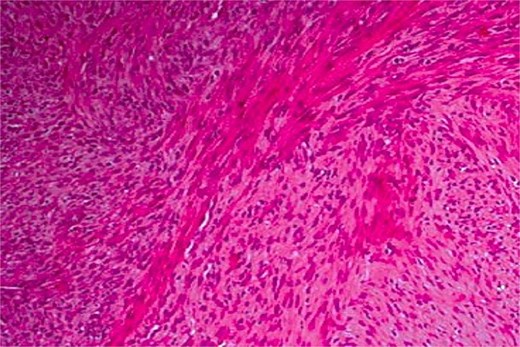

The patient underwent wide surgical resection, including dental extractions and bone curettage (Fig. 3). He then received external beam radiotherapy (65 Gy).

Haematoxylin and eosin stain at ×100 magnification showing a leiomyosarcoma composed of perpendicularly oriented fascicles of spindle-shaped cells.

Histopathologically, leiomyosarcoma is characterized by spindle-shaped cells with eosinophilic cytoplasm and elongated nuclei in fascicular patterns. Immunohistochemistry, including desmin and smooth muscle actin, helps differentiate it from other spindle-cell neoplasms [4], with calponin improving diagnostic specificity [5].